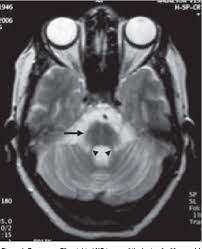

Fitness hot cross buns on cutting cartoon vector illustration. Few reports have evaluated the sensitivity of an hcb, including a cruciform. The hot cross bun sign is a radiological sign which has been said to be highly specific for multiple system atrophy. Hot cross buns are traditionally eaten on good friday on the british isles and some parts of the commonwealth such as canada and australia. The white strips represent degenerated pontine white matter pathways within the pons. Serve these warm from the oven on good friday to wow your family and friends. And friends who gift one another with hot cross buns every year. A hot cross bun is a spiced sweet bun usually made with fruit, marked with a cross on the top, and traditionally eaten on good friday in the united kingdom; Some sailors took hot cross buns on their voyages to ensure their ships wouldn't sink. The hot cross bun sign refers to the mri appearance of the pons when t2 hyperintensity forms a cross on axial images, representing selective degeneration of transverse pontocerebellar tracts and median pontine raphe nuclei. Find the perfect hot cross bun stock illustrations from getty images. If you flip to the 'bun: Oligodendrocytes comprise glial cytoplasmic inclusions (gci).

A hot cross bun is a spiced sweet bun usually made with fruit, marked with a cross on the top, and traditionally eaten on good friday in the united kingdom; Detective the hot cross buns character homemade vector illustration. Signo de la cruz (hot cross bun sign). Oligodendrocytes comprise glial cytoplasmic inclusions (gci). Hot cross buns is the perfect song for beginners: Few reports have evaluated the sensitivity of an hcb including a cruciform. And friends who gift one another with hot cross buns every year. It is the only relic that appears if the entire item pool has been exhausted. Hot cross bun sign in multiple system atrophy with predominant cerebellar ataxia: Key word signing uses a core. What are hot cross buns? Hot cross buns sign is a vommon radiographic finding in msa. Cerebellum and middle cerebellar peduncles are also atrophied.

Find the perfect hot cross bun stock illustrations from getty images. Few reports have evaluated the sensitivity of an hcb including a cruciform. 'hot cross bun' sign with leptomeningeal metastases of breast cancer: Signo de la cruz (hot cross bun sign). World j surg oncol 2015;13:43. If you flip to the 'bun: Shops may still have a few more relics for sale; In the reign of elizabeth i, when roman catholicism was banned, making the sign of the cross on the buns was regarded as popery and the practice was banned. Lent icon vector isolated on white background, logo concept of lent sign on transparent background, filled black symbol. A hot cross bun is a spiced sweet bun usually made with fruit, marked with a cross on the top, and traditionally eaten on good friday in the united kingdom; 6 count (pack of 2). Hot cross bun is a relic in undermine. The buns come out sweet and soft with hints of warm spices, orange zest and studded with raisins.